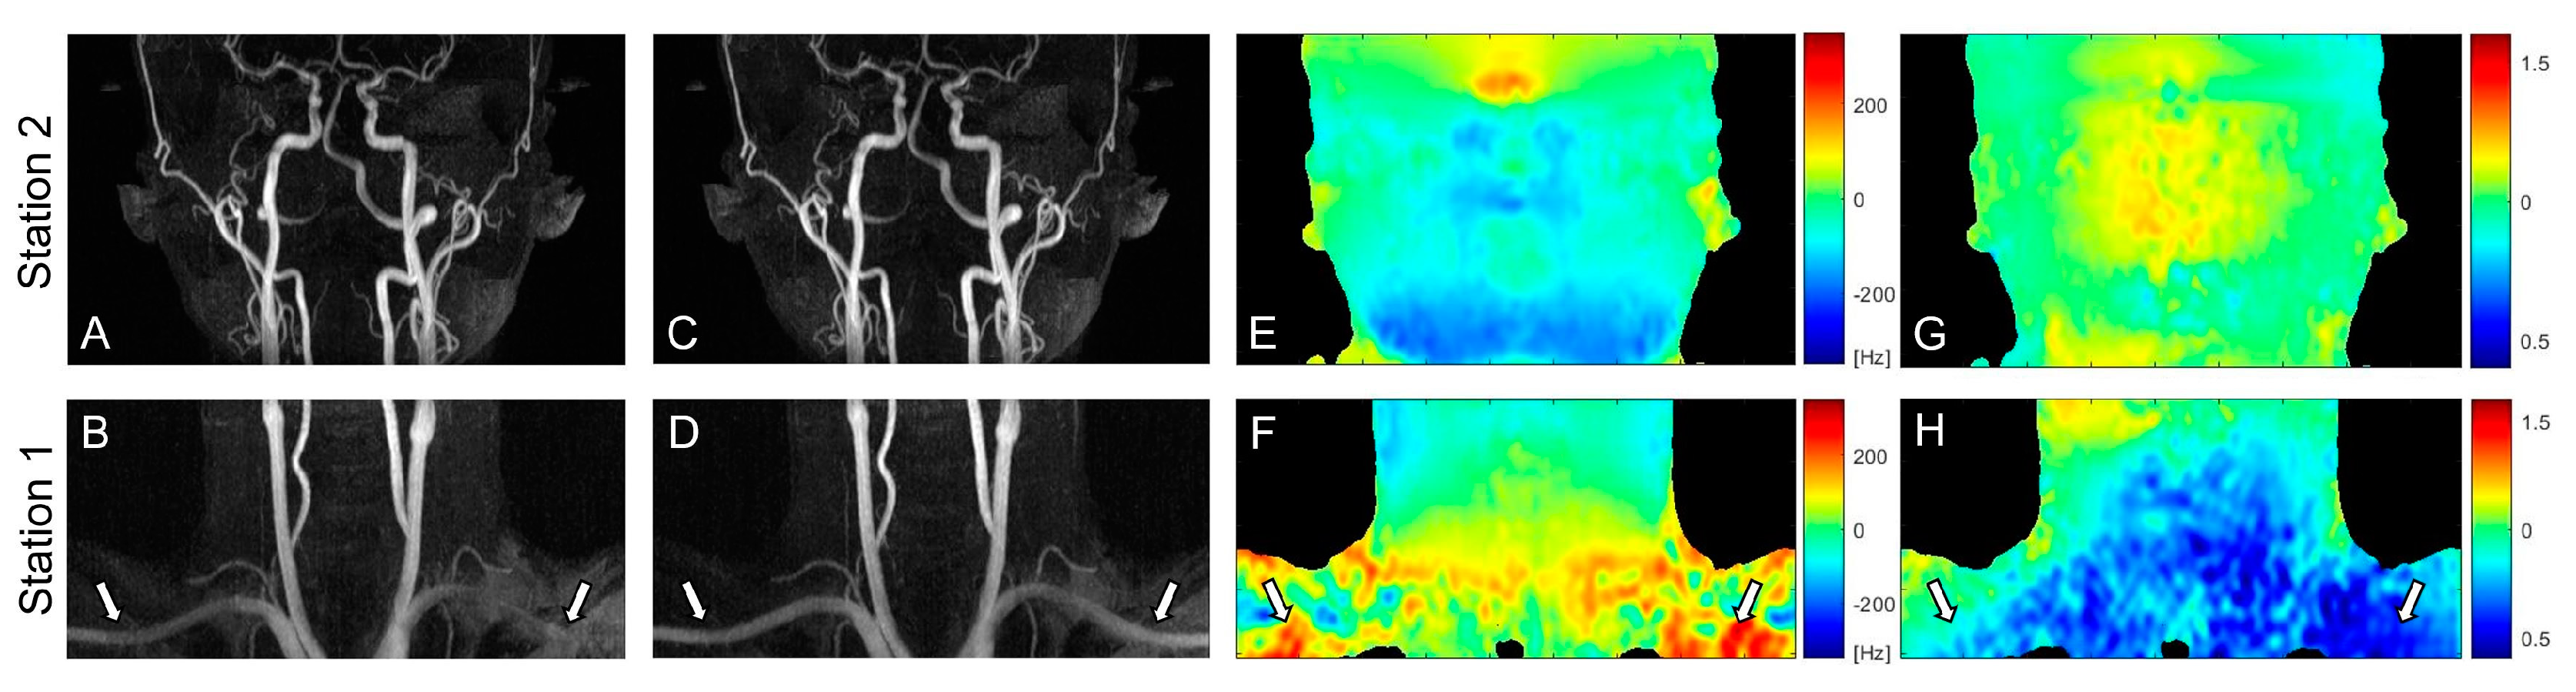

3.1. PC Flow and Field Mappings